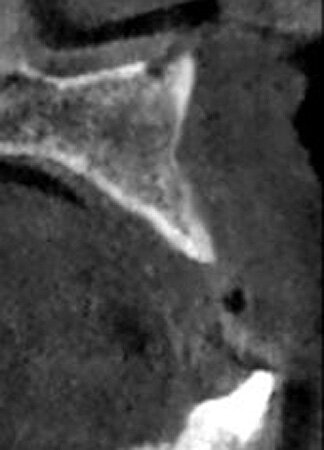

A 52-year-old male patient presented missing the left central and lateral maxillary incisors with a desire to have implants to replace the missing teeth and a fixed prosthetic approach. The patient indicated that the teeth had been extracted eight years before, and clinical examination noted a deficient facial aspect of the ridge at the extraction sites and healthy soft tissue (Fig. 1). A cone-beam CT (CBCT) was taken and evaluated. Cross-sectional views of the edentulous space confirmed inadequate width of the ridge in the facial-palatal dimension to house implants at the adjacent sites (Fig. 2). The patient was informed of the clinical findings and a discussion on augmenting the site with an osseous graft would be necessary for implant placement. As insufficient bone would not permit simultaneous implant placement at the time of grafting, the patient was informed that a healing period of four to six months would be needed between graft placement before implants could be placed. This would then be followed by a four- to six-month period to allow the implants to osseointegrate before any restoration could be placed on the implants. The patient agreed to treatment and was appointed.

Fig. 2: CBCT cross-section demonstrating insufficient ridge width facial-palatally to permit implant placement in the healed extraction sites.